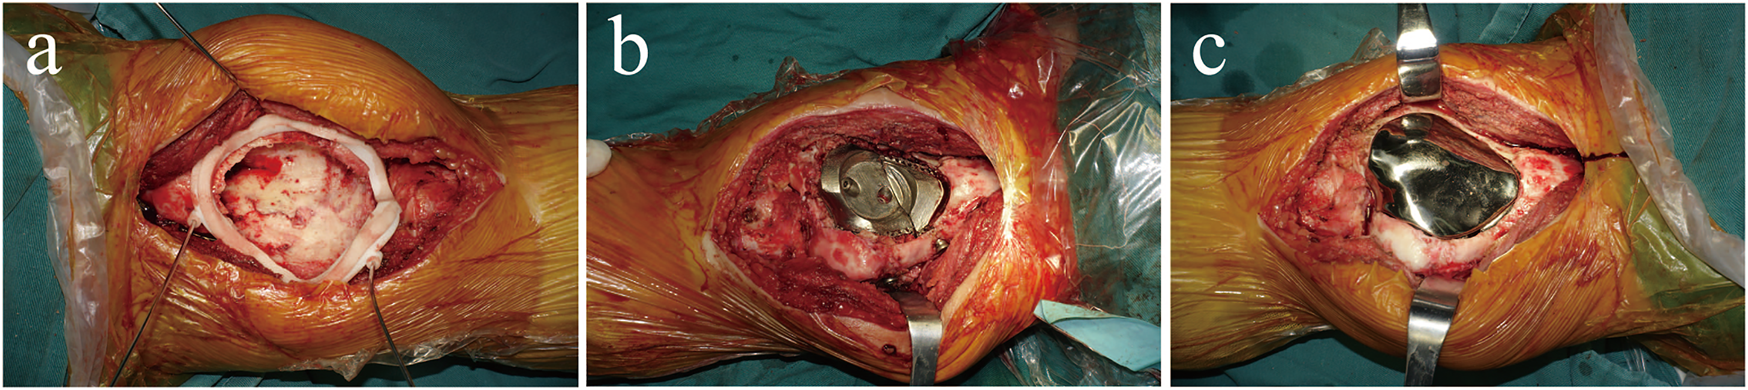

Surgical procedure

Surgery was performed using an anteromedial approach under general anaesthesia. After bone cement removal, the bony cortex around the tumour 1–2 mm was excised using a circular 3D-printed guided plate (Figure 4A). The tumour cavity was then cauterised with an electric knife, expanded with a high-speed burr, and irrigated with anhydrous alcohol and distilled water. The back components were inserted into the cavity and fixed to the surrounding bone with four screws (Figure 4B). Autogenous iliac bone was inserted into the gap between the prosthesis and the adjacent bone to facilitate bone ingrowth. The front modular component was firmly fixed on the back components through a press-fit structure (Figure 4C). The surgery took 325 min, the intraoperative blood loss was 400 ml, and postoperative X-ray images showed that the implant was in a good position (Figures 5A,B).

FIGURE 4

(A) The circular 3D-printed guided plate is fixed on the bone margin of the tumour. (B) The back components are inserted into the bone cavity and firmly fixed to the surrounding bone with four screws. (C) The front component is firmly fixed on the back components through a press-fit structure and conforms to the surrounding articular surface.